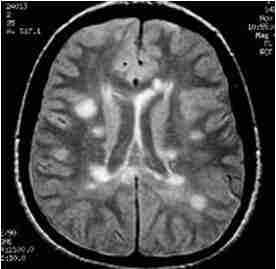

При МРТ головного мозга могут встречаться сочетания центрального понтинного миелпноза и экстрапонтинного миелиноза. Экстрапонтинный миелиноз на Т2-взвешенных МРТ головного мозга виден как гиперинтенсивные очаги в области подкорковых ядер.

МРТ головного мозга. Т2-взвешенная аксиальная МРТ. Центральный понтинный миелиноз.

МРТ головного мозга. Аксиальная Т2-взвешенная МРТ типа FLAIR. Экстрапонтинный миелиноз.